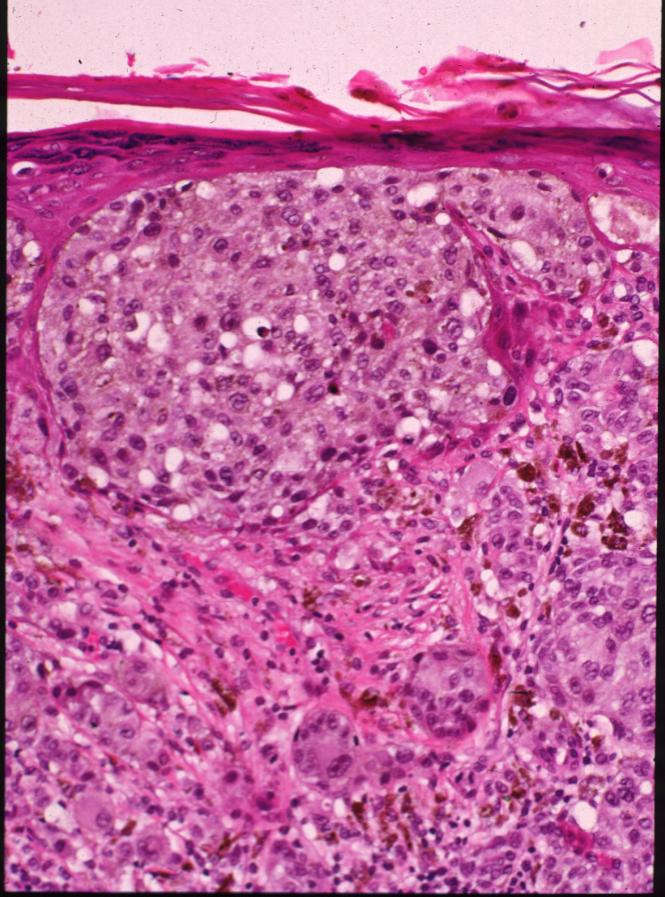

malignant-melanoma